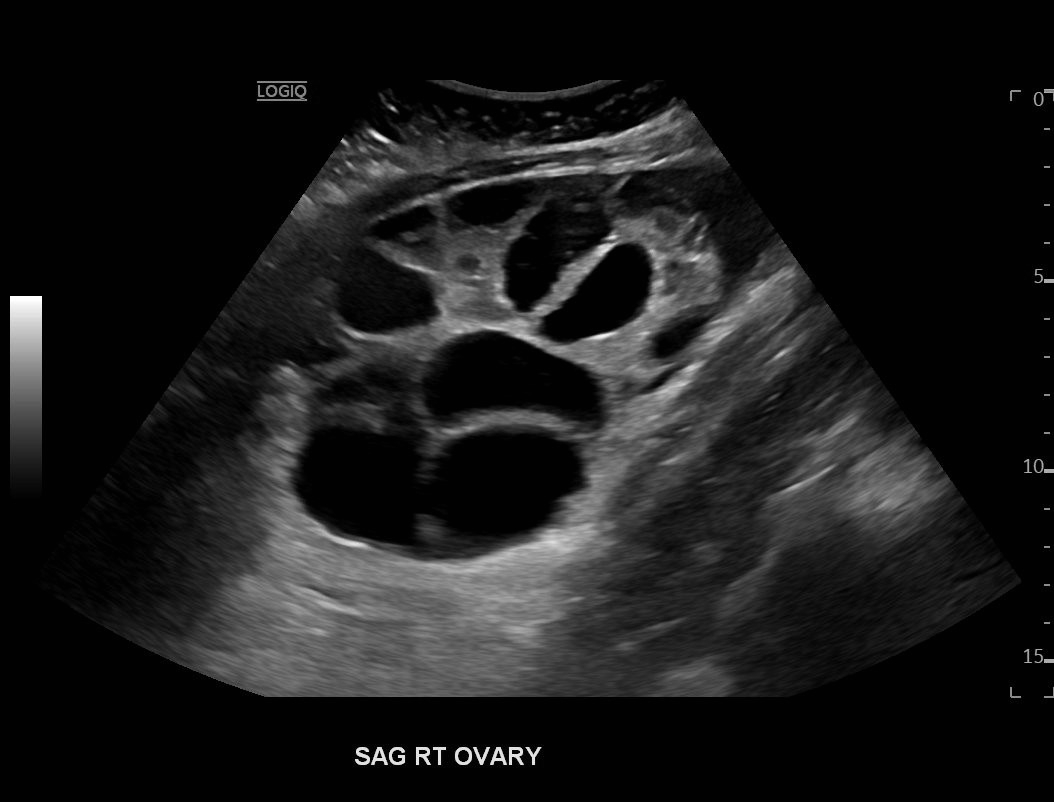

Ovarian hyperstimulation syndrome (OHSS) is a potentially life-threatening complication of assisted reproductive technology (ART). Here, we present the case report of a 30-year-old female undergoing infertility treatment who presented to the emergency department (ED) with nausea and vomiting, abdominal distention, and shortness of breath. On physical exam, she had notable ascites. Computed tomography (CT) of the abdomen and pelvis and pelvic ultrasound (US) revealed significant ascites and enlarged ovaries with multiple cysts. She was diagnosed with severe OHSS and admitted to obstetrics and gynecology (OBGYN) service for five days where she underwent intravenous (IV) hydration and paracentesis. This case report reviews the clinical presentation, categorization, management, and prevention of OHSS and provides examples of imaging findings consistent with the condition.